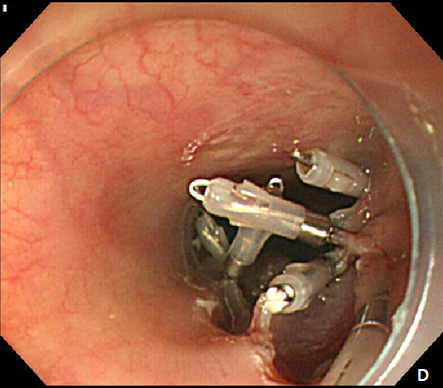

A 61-year -old woman was refferred to our hospital for further evaluation of esophageal SET. She hassuffered fromdysphagiafor many years, and an EGD showed a large, 3.5 cm sized, elongated SET at upper esophagus, 22 cm from incisor, and it showed positive rolling sign (Figure 4). As the conventional ESD is expected to cause post-procedural stricture of esophagus, we decided to perform subepithelial tunnelling endoscopic resection (STER) method to preserve mucosal integrity and prevent stricture. STER was performed according to previously suggested protocols.3 Briefly, a mixed solution of epinephrine in saline (1:10,000) was injected at submucosal layer, and a 2.0cm longitudinal mucosal incision was made to gain entry to the submucosal area and a submucosal tunnel was created 5.0 cm proximal to the SET until the tumor was visible by an endoscope while carefully preserving the covering mucosal integrity After exposure of the SET, complete dissection of the tumor was carefully performed using an IT knife along the margin. After dissection, mucosal integrity was preserved well, and the mucosal entry site was closed with standard hemostatic clips (HX-610-90, Olympus Optical Co Ltd.) (Figure 5A-5D). The resected specimen was 3.5 cm in length and 1.7 cm in diameter, and tumor was diagnosed as leiomyoma by histopathologic examination. The patietns had no immediate major complications, and discharged 3 days after the procedure. A follow-up EGD was performed at 6 and 24 months after the procedure, which showed no significant stricture, and only scar change was noted on the mid esophagus (Figure 6).

Figure 5 Submucosal tunneling endoscopic resection (STER) of esophageal subepithelial tumor (SET).

(A) Submucosal tunneling was made to approach and expose the tumor. (B) Dissection of the tumor was performed by using an insulated-tip knife. (C) After resection of the tumor, mucosal integrity was preserved as flat. (D) Entry site was sealed by using endoscopic clips.